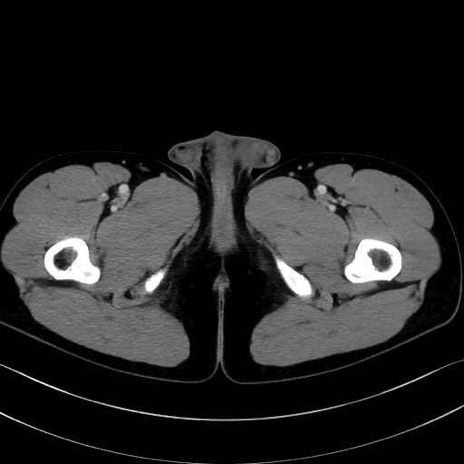

5. 大腿前面(大腿四頭筋群・伸筋群)

縫工筋 (Sartorius)

大腿直筋 (Rectus femoris)

外側広筋 (Vastus lateralis)

中間広筋 (Vastus intermedius)